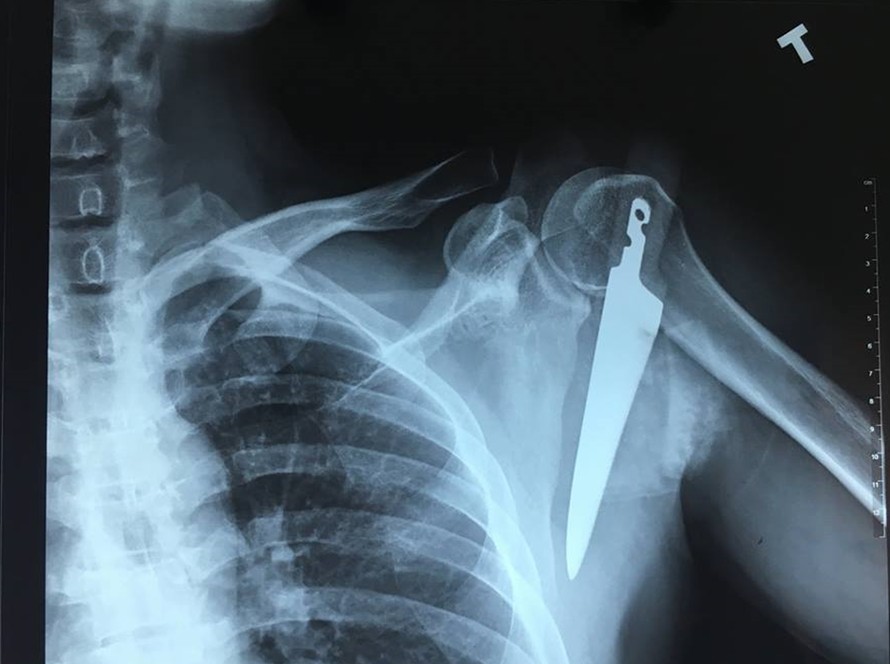

Hình ảnh phim chụp con dao đâm sâu vào vai trái bệnh nhân. (Ảnh: Bệnh viện cung cấp)

Báo Lao động đưa tin, ngày 13/2, Bệnh viện Việt Nam – Thụy Điển Uông Bí cho biết, ngày 8/2, anh L.T.T. (35 tuổi ở Uông Bí, Quảng Ninh) nhập viện với một con dao găm sâu vào vai trái.

Chia sẻ với Zing.vn, các bác sĩ điều trị thông tin, người bệnh nhập viện với một con dao găm ngập cán vào vùng vai trái ngay dưới xương đòn, mất nhiều máu. Vị trí này gần ngay các động mạch lớn và đám rối thần kinh cánh tay. Nếu không được tiến hành phẫu thuật cấp cứu kịp thời, người bệnh sẽ phải đối mặt với nguy cơ như chảy máu nhiều, mất máu, nhiễm trùng, có thể tử vong.

Các bác sĩ đã nhanh chóng tiến hành phẫu thuật cấp cứu lấy con dao ra khỏi vùng vai trái của người bệnh, nối cơ, xử lý vết thương cho người bệnh.

Con dao được lấy ra sắc, nhọn có chiều dài hơn 20 cm. Hiện tại sức khỏe người bệnh ổn định, vết mổ khô và sẽ được xuất viện trong vài ngày tới.